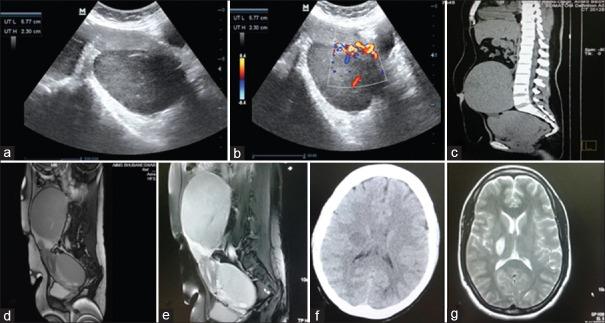

Primary ovarian lymphoma is extremely rare. We report a case of primary T-cell lymphoblastic lymphoma of the ovary in a 31-year-old multiparous woman, who presented with abdominal pain. Her menstrual cycles were regular. There was no generalized lymphadenopathy or fever. On per abdominal examination, there was a firm, tender, solid, mobile mass with well-defined borders, corresponding to 20 weeks gestation, whose lower pole was easily reached. Per vaginum examination revealed a large adnexal mass in the right and anterior fornix. Transabdominal ultrasonography showed bilateral solid ovarian tumor measuring 13.9 cm × 11.8 cm on the right side and 10.0 cm × 6.3 cm on the left side with significant vascularity. Tumor markers were within normal limit except for significantly elevated serum lactate dehydrogenase. Magnetic resonance imaging showed two large solid homogeneous masses, hypointense on T1W1 and hyperintense on T2W1 imaging, with a normal sized uterus and no ascites or lymphadenopathy. The patient developed one episode of left hemiparesis preoperatively, which improved spontaneously. Staging laparotomy with total abdominal hysterectomy and bilateral salpingo-oophorectomy along with infracolic omentectomy was done. Histopathology with immunohistochemistry revealed primary T-cell lymphoblastic lymphoma of the ovary, involving both ovaries left fallopian tube and left serosal surface of fundal region of uterus. She developed generalized convulsions on the 12 postoperative day, and final diagnosis was primary ovarian T-cell lymphoblastic lymphoma Ann Arbor Stage IV. She received three cycles of chemotherapy with cyclophosphamide, doxorubicin, vincristine, and prednisolone regimen and was on palliative care. She succumbed to her illness 5½ months postoperatively.

原发性卵巢淋巴瘤极为罕见。我们报告一例31岁经产妇的原发性卵巢T细胞淋巴母细胞淋巴瘤病例,该患者表现为腹痛。她的月经周期规律。无全身淋巴结肿大或发热。腹部检查时,可触及一个质地硬、有压痛、实性、可活动且边界清晰的肿块,大小相当于妊娠20周,其下极易于触及。经阴道检查发现右侧及前穹窿有一个大的附件肿块。经腹超声检查显示双侧实性卵巢肿瘤,右侧大小为13.9 cm×11.8 cm,左侧为10.0 cm×6.3 cm,血流丰富。除血清乳酸脱氢酶显著升高外,肿瘤标志物均在正常范围内。磁共振成像显示两个大的实性均匀肿块,在T1加权成像上呈低信号,在T2加权成像上呈高信号,子宫大小正常,无腹水或淋巴结肿大。患者术前出现一次左侧偏瘫,后自行好转。进行了分期剖腹手术,包括全腹子宫切除术、双侧输卵管卵巢切除术以及结肠下网膜切除术。组织病理学及免疫组化检查显示为原发性卵巢T细胞淋巴母细胞淋巴瘤,累及双侧卵巢、左侧输卵管及子宫底部左侧浆膜面。患者术后第12天出现全身性惊厥,最终诊断为原发性卵巢T细胞淋巴母细胞淋巴瘤,Ann Arbor分期为IV期。她接受了三个周期的环磷酰胺、阿霉素、长春新碱和泼尼松龙方案化疗,目前接受姑息治疗。她术后5个半月因病去世。